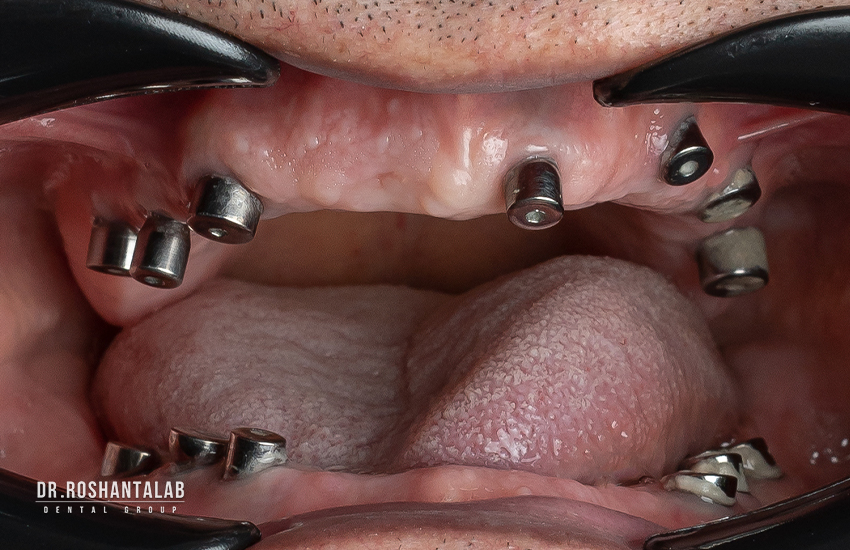

در روش جراحی کاشت ایمپلنت دیجیتالی ابتدا باید وضعیت فک، دندانها، عصبها، لثه، عروق و سینوس فرد مورد بررسی قرار گیرد که به تهیه عکس رادیوگرافی سهبعدی از فک (cbct) نیاز است. قدم بعدی تهیه اسکن از دندانها و لثههای بیمار است. متخصص ایمپلنت پس از گرفتن تصاویر رادیوگرافی با استفاده از تکنولوژی شبیهسازی سهبعدی پردازشهای لازم را انجام میدهد.

پس از پردازش، مناسبترین وضعیت کاشت ایمپلنت دیجیتال طراحی شده و بهترین طول و قطر ایمپلنت با توجه به کیفیت استخوان فک، جایگاه عصب و سینوس تعیین میشود. در این مرحله نیاز است که طرح توسط ایمپلنتولوژیست تایید شود. پس از تایید طرح، با استفاده از پرینتر سهبعدی، راهنما یا گاید که از جنس پلاستیک شفاف است، ساخته میشود.

وقتی گاید جراحی آماده شد دندانپزشک آن را در دهان شما قرار میدهد و ایمپلنت را با دقت بسیار بالا و نهایت صبر و حوصله در جایی که قبلا آن را تعیین کرده بود، میکارد.

- مرحله پنجم: کار گذاشتن ایمپلنت دندان

- مرحله هفتم: کار گذاشتن اباتمنت یا پایه تاج